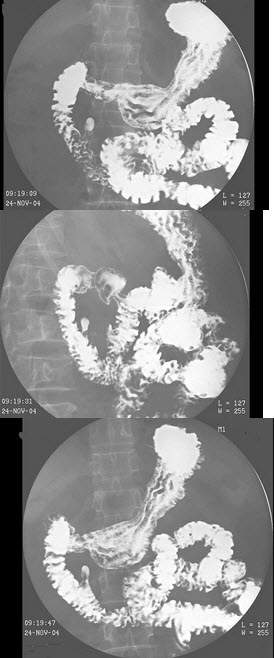

177、多项选择题

女,48岁,中上腹不适,结合图像,最可能的诊断为()

A.正常表现

B.胃炎

C.胃癌

D.十二指肠憩室

E.十二指肠占位

点击查看答案